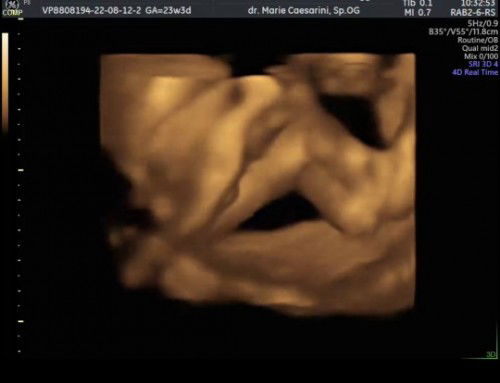

USG Cek jenis kelamin di 23 Weeks

Haloo bundaa... mau tanya dong, kalo kayak gini itu baby nya Girl or boy ya ? Soalnya ketutupan paha si dedek mulu. Kata dokternya kemungkinan cowok, tapi belum kelihatan jelas, jadi masih penasaran. Bantu jawab dong bund. Mungkin yg udah2 lebih berpengalaman. Terima kasih #seriusnanya #bantusharing #ingintahu #firstmom #pleasehelp